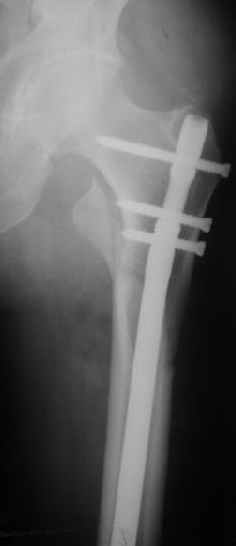

В частности, на проксимальном конце сделано еще одно дополнительное статическое отверстие. Можно ввести в проксимальном отделе 4 винта, из них 3 статические (2 в круглые отверстия и 1 по нижнему краю овального). Картинки в приложении. На дистальном конце стержня тоже кое-что улучшено. Спрашивайте в аптеках, как говорится. Выпускается предприятием "ЦИТО" (Москва), то есть это малобюджетное решение.

Конечно, мы не синтезируем остеопорозые вертельные переломы согласно прилагаемому примеру, винты 6 мм вырежутся. Но у более молодых при хорошем качестве кости такие или подобные гвозди с поперечным расположением винтов вполне применимы для меж- и подвертельных переломов.

Это было года 2,5 назад, мы тогда еще уточняли возможности шинирования с угловой стабильностью гвоздем с поперечным расположением винтов при переломах проксимального отдела бедра. Пациенту не пришлось приобретать намного более дорогой рекон или проксимальный гвоздь. В приложении еще несколько примеров применения того гвоздя при высоких переломах бедра, в том числе с более латеральной точкой входа. Гвоздь изгибаем для этого.